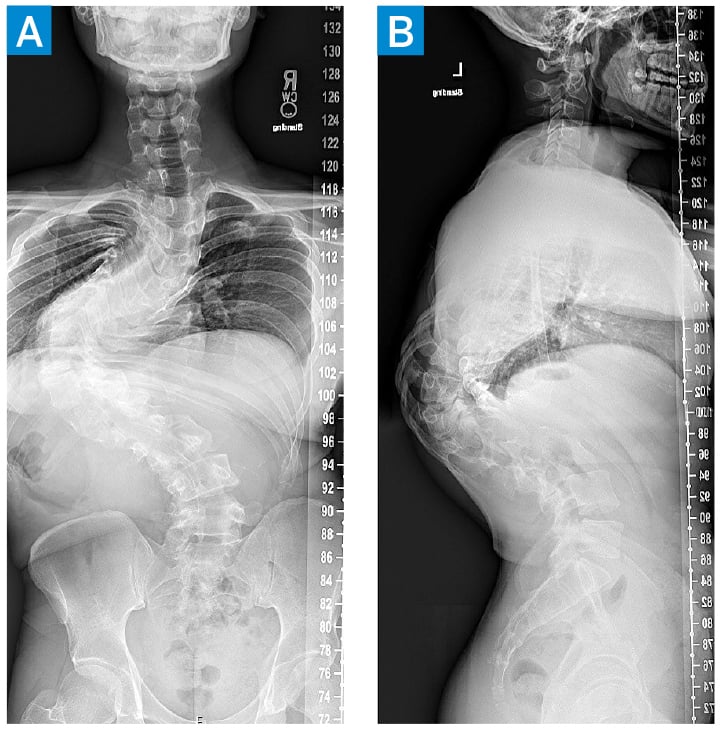

Scoliosis films showed a 135° apex left thoracic Cobb angle with a 75° thoracic kyphosis (Fig. 1). Magnetic resonance imaging (MRI) of the cervical, thoracic, and lumbar spine did not show notable spinal stenosis or spinal cord anomalies. Pulmonary function testing showed significant restrictive lung disease.

Figure 1: Posteroanterior (A) and lateral (B) scoliosis radiographs show a 135° apex left thoracic curve with a 75° thoracic kyphosis.